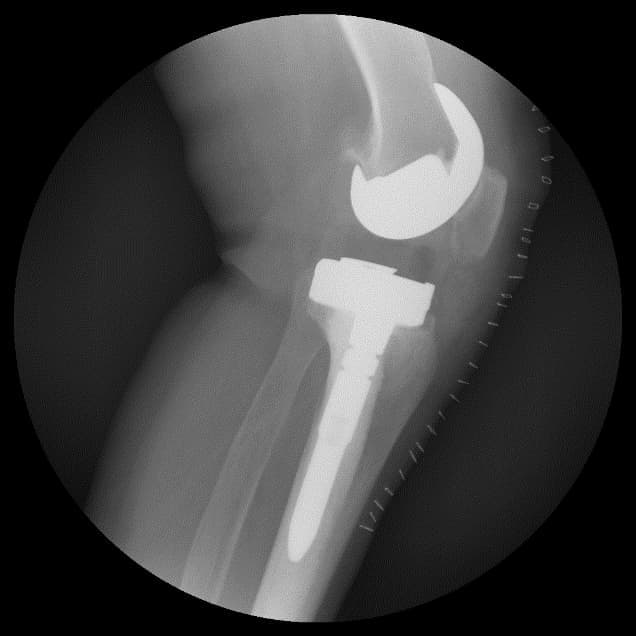

Тохиолдол танилцуулга 5.

Өвчтөн: Д.Г 65 настай, 2019.1.4 эрэгтэй

Сэргээн засах мэс засал: Өвдөгний үе сэргээх тусгай протез суулгах мэс засал.

Үе дайрсан ясны анхдагч хавдар, ясны дутмагшлын үед хийгдэх мэс засалimg22Үе дайрсан ясны анхдагч хавдар, ясны дутмагшлын үед хийгдэх мэс засалimg23

Зураг 1. Сэргээн засах мэс заслын өмнөх рентген зураг. Эгц урд, хажуугаас авсан байдал.

Үе дайрсан ясны анхдагч хавдар, ясны дутмагшлын үед хийгдэх мэс засалimg24Үе дайрсан ясны анхдагч хавдар, ясны дутмагшлын үед хийгдэх мэс засалimg25

Зураг 2. Мэс заслын дараах рентген зураг. Эгц урд, хажуугаас авсан байдал

Өвдөгний үений шөрмөсөн холбоосууд үрэвслийн улмаас бүрэн гэмтсэн Дунд чөмөг - шилбэ ясны дутмагшилтай учир дунд чөмөг-өвдөгний хавдрын протез сонгон суулгасан. Энэ дунд чөмөг-өвдөгний хавдрын протез нь мөн hinge system- тэй.